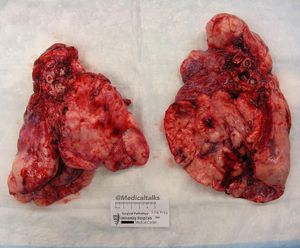

This is a sample of lungs affected by cystic fibrosis removed from Kara, a young female that was suffering from an end-stage lung disease of cystic fibrosis and was completely oxygen dependent. Cystic fibrosis is an inherited disease of the exocrine glands caused by a mutation in the CF transmembrane conductance regulator gene. This defect results in tenacious secretions accumulating in ducts throughout the body, such as lungs, pancreas, and vas deferens. In simpler terms, characterized by the buildup of thick, sticky mucus that can damage the respiratory and digestive systems. This abnormal mucus and defective mucociliary clearance of inspissated secretions permits accumulation of debris and bacteria in the airway, resulting in recurrent sinopulmonary infections. These infections cause severe acute pulmonary exacerbation, as evidenced by hypoxia and respiratory distress. Over time, it results in permanent lung damage, including the formation of scar tissue (fibrosis) and cysts in the lungs. On March 10, 2017, she received a double lung transplant. A lung transplant is not a cure though, she still has CF. This picture shows CF lungs that were extremely diseased. She lived with those lungs for 34 years. She couldn’t breathe, and coughed up blood all the time. Back years ago, kids with CF didn’t live to see their teenage years.The life span with a CF’er is around 50, some people are older than 50 and still fighting. Credit to @kara.lynette83